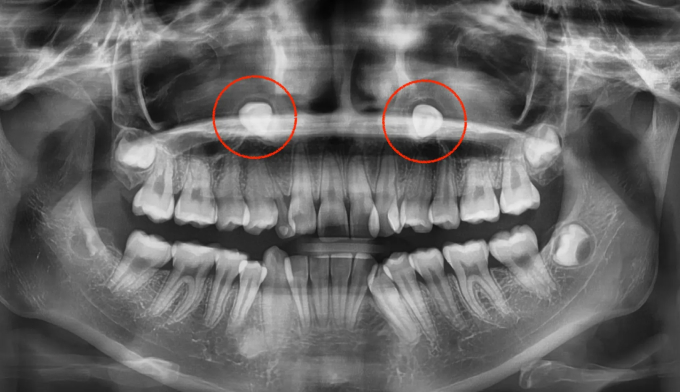

위쪽 송곳니가 엑스레이상에서도 거의 코 옆쪽으로 매복되어 있는 케이스입니다.

매복치에 접근하는것이 무리라고 판단되어 유치만 발치하고 진행하기로 하였습니다.